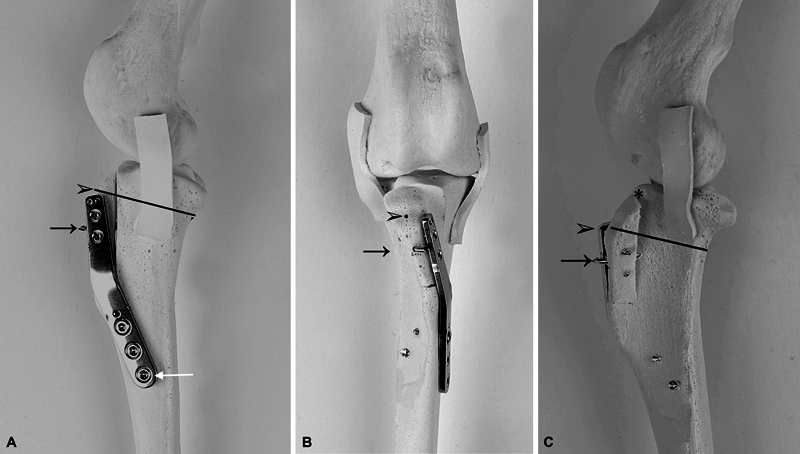

Objectives:  To evaluate the outcome and complications in dogs with medial patellar luxation (MPL) undergoing tibial tuberosity transposition (TTT) with a locking plate and pin fixation (Plate-Pin).

Methods:  This retrospective multicenter study included 65 consecutive MPL stifle surgeries using tibial tuberosity (TT) fixation with a 5-hole locking plate and a pin. The median weight of the dogs was 6.2 kg. The grade of luxation was 2/4 in 50 stifles and 3/4 in 15 stifles. Outcomes were assessed during follow-up examinations 33 to 648 days after surgery with clinical examination and radiography. Canine Orthopedic Index questionnaires were sent to owners 6 to 39 months after surgery.

Clinical significance:  When the surgery was performed as described in this article, Plate-Pin fixation for TT during MPL surgery is a feasible technique with a lower incidence of luxation recurrence, TT avulsion, and fractures compared with recent retrospective studies with pin and tension band wire TT fixation. Further development of the locking plate TT fixation is indicated to resolve pin-related complications and to determine if fixation including a pin is necessary.

Abstract Image